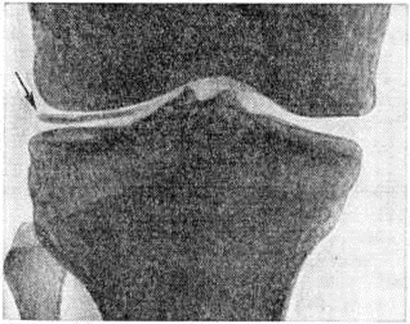

Рентгенологические признаком Псевдоподагра является хондрокальциноз — обызвествление хряща в виде теней или отдельных вкраплений. Обызвествлению при Псевдоподагра подвергается не только гиалиновый хрящ (наиболее часто коленных суставов), но и волокнистая хрящевая ткань (мениски, хрящ лонного сочленения, хрящевой диск в области кистевого сустава, межпозвонковые диски), а в некоторых случаях и соединительная ткань капсулы суставов, сухожилий и сумок. Наиболее типичен для Псевдоподагра хондрокальциноз менисков коленных суставов (рисунок). Рентгенологические исследование имеет важное диагностическое значение при Псевдоподагра В ряде случаев хондрокальциноз поражённого в данный момент сустава при Псевдоподагра может отсутствовать, поэтому для уточнения диагноза необходимо исследование других наиболее частых локализаций хондрокальциноза, указанных выше. При Псевдоподагра часто наблюдаются рентгенологическое изменения, характерные для артроза — деструкция суставного хряща и развитие остеофитов (смотри полный свод знаний).